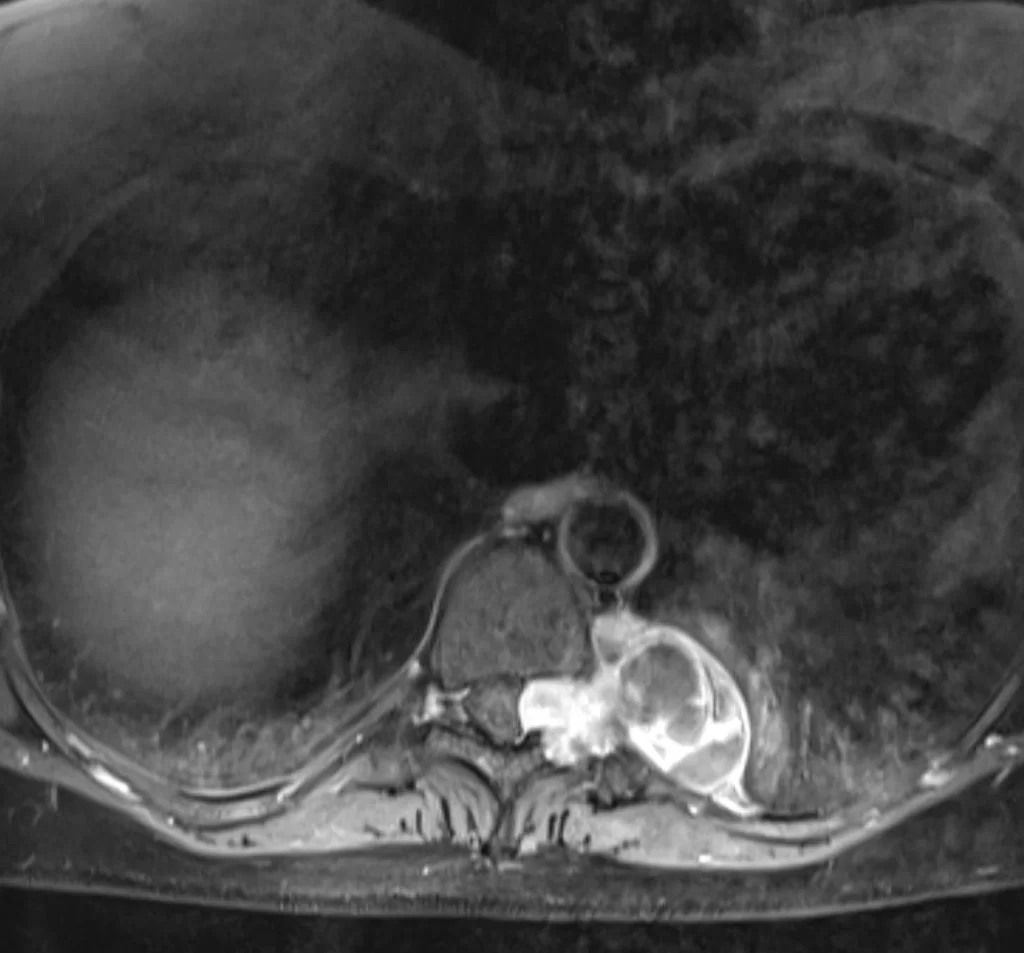

Ο απεικονιστικός έλεγχος με μαγνητική τομογραφία ανέδειξε ευμεγέθη ενδο/εξωκαναλική χωροκατακτητική εξεργασία στο ύψος Θ9/10 αριστερά, ύποπτη για σβάννωμα.

Το συγκεκριμένο σβάννωμα παρουσίαζε σημαντικό εξωκαναλικό κομμάτι (δηλαδή όγκο με επέκταση πέρα απο τη σπονδυλική στήλη και το νωτιαίο μυελό), με πίεση του αριστερού πνεύμονα αλλά και στενή γειτνίαση με τα μεγάλα αγγεία του θώρακα. Παρόλα αυτά, όπως φαίνεται και από την μετεγχειρητική μαγνητική τομογραφία ο όγκος αφαιρέθηκε ολικά, χρησιμοποιώντας μόνο οπίσθια προσπέλαση.